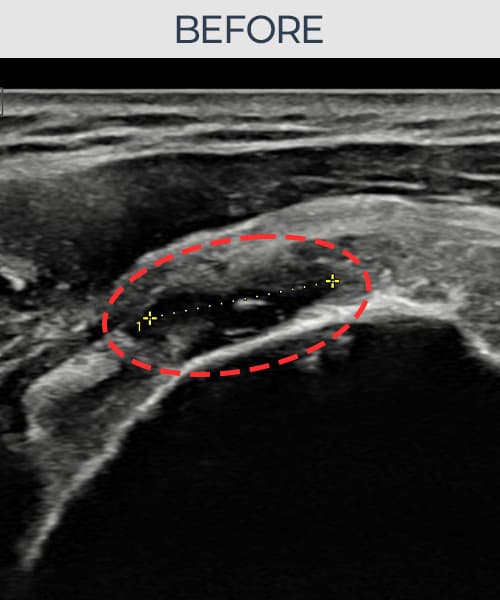

시술 전 초음파 측정 결과 파열 크기는 14mm × 7mm (힘줄 두께의 약 68% 결손)로 확인되었습니다. 시술 전 초음파에서 6개월 이상 방치로 인한 관절면측 회전근개 결손과 힘줄 위축 소견이 관찰되었습니다. 시술 후 초음파에서 파열 부위의 인대 연속성이 완전히 회복되었고, 인대 두께가 정상 범위로 복원된 것이 확인되었습니다.

70대 초반 남성 환자분으로, '나이 들면 으레 아픈 거겠지' 하며 6개월 이상 진통제로만 버티다 보행과 수면에 지장이 생겨서야 내원하셨습니다. 내원 당시 어깨를 90도 이상 올리기 어려운 상태였으며, 초음파 검사에서 관절면측 회전근개의 결손과 인대 위축이 상당히 진행된 것이 확인되었습니다. 고령임에도 전신 상태가 양호하고 파열이 관절면측에 국한되어 있어 비수술 축소봉합술이 적합하다고 판단하였습니다. 시술 후 보조기 착용 및 충분한 회복 기간을 확보하였으며, 65세 이후 조직 회복 속도를 고려해 재활 일정을 보수적으로 운영하였습니다. 시술 3개월 후부터 진통제 없이 수면이 가능해지셨고, 최종 경과 관찰에서 인대 연속성이 완전히 회복되어 일상 보행과 가벼운 운동이 가능한 상태가 되셨습니다.